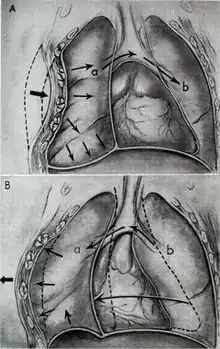

Blunt thoracic trauma

The term blunt thoracic trauma, or, more informally, blunt chest injury, encompasses a variety of injuries to the chest. Broadly, this also includes damage caused by direct blunt force (such as a fist or a bat in an assault), acceleration or deceleration (such as that from a rear-end automotive crash), shear force (a combination of acceleration and deceleration), compression (such as a heavy object falling on a person), and blasts (such as an explosion of some sort). Common signs and symptoms include something as simple as bruising, but occasionally as complicated as hypoxia, ventilation-perfusion mismatch, hypovolemia, and reduced cardiac output due to the way the thoracic organs may have been affected. Blunt thoracic trauma is not always visible from the outside and such internal injuries may not show signs or symptoms at the time the trauma initially occurs or even until hours after. A high degree of clinical suspicion may sometimes be required to identify such injuries, a CT scan may prove useful in such instances. Those experiencing more obvious complications from a blunt chest injury will likely undergo a focused assessment with sonography for trauma (FAST) which can reliably detect a significant amount of blood around the heart or in the lung by using a special machine that visualizes sound waves sent through the body. Only 10–15% of thoracic traumas require surgery, but they can have serious impacts on the heart, lungs, and great vessels.[12]

The most immediate life-threatening injuries that may occur include tension pneumothorax, open pneumothorax, hemothorax, flail chest, cardiac tamponade, and airway obstruction/rupture.[12]

The injuries may necessitate a procedure, most commonly the insertion of an intercostal drain, or chest tube. This tube is typically installed because it helps restore a certain balance in pressures (usually due to misplaced air or surrounding blood) that are impeding the lungs' ability to inflate and thus exchange vital gases that allow the body to function.[13] A less common procedure that may be employed is a pericardiocentesis, which, by removing blood surrounding the heart, permits the heart to regain some ability to appropriately pump blood.[14][15] In certain dire circumstances an emergent thoracotomy may be employed.[16]

Treatment of blunt thoracic trauma

Nine out of ten patients with thoracic trauma can be treated effectively without a surgical operation.[37] If surgery is indicated, there are numerous options available. A comprehensive discussion between the patient and the surgeon will take place to carefully evaluate the best approach, tailored to the patient's specific condition and injury. Conservative measures such as maintaining a clear and open airway, oxygen support, tube thoracostomy, and volume resuscitation are often given to manage blunt thoracic trauma.[37] Oftentimes, pain control is the most basic and effective treatment approach because the presence of severe pain may lead to impairment of proper breathing, further exacerbating impaired lungs.[37] Pain management in thoracic trauma patients improves the ability to breathe properly on their own, encourages the excretion of pulmonary secretions, and decreases the aggravation of inflammation and low oxygen levels in the blood.[37] Nonsteroidal anti-inflammatory drugs, opioids, or regional pain management methods, such as local anesthetic, can be used for pain control.[37]